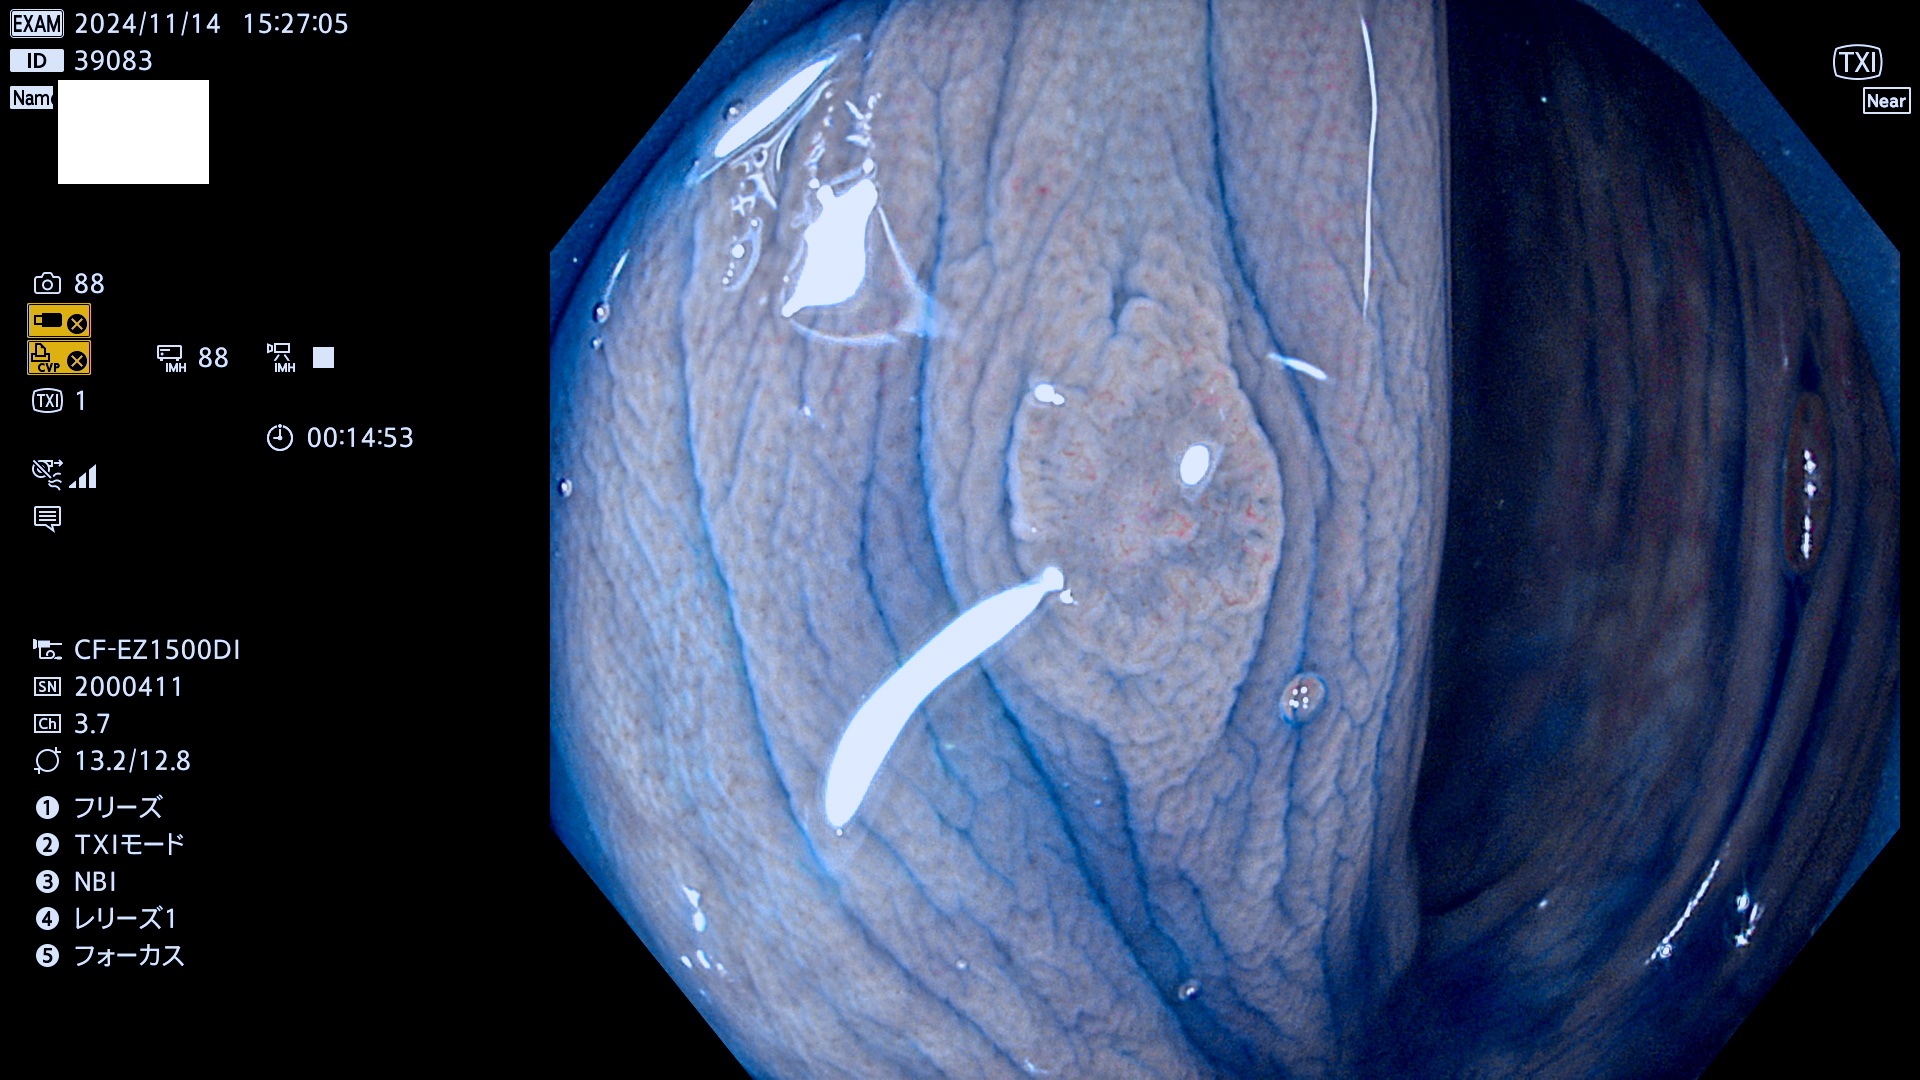

完全に平坦な物をUb、陥凹している物をUcと呼びます。最も発見が難しく危険な病変です。

毎週の検査(木・金・土・日)に発見されたUb、Uc型・腺腫を、その週の日曜の夜にUPし1週間、提示します。

抽出の対象期間 2024年11月14日〜11月17日の4日間(48件の検査)7件 (7/48=14%)